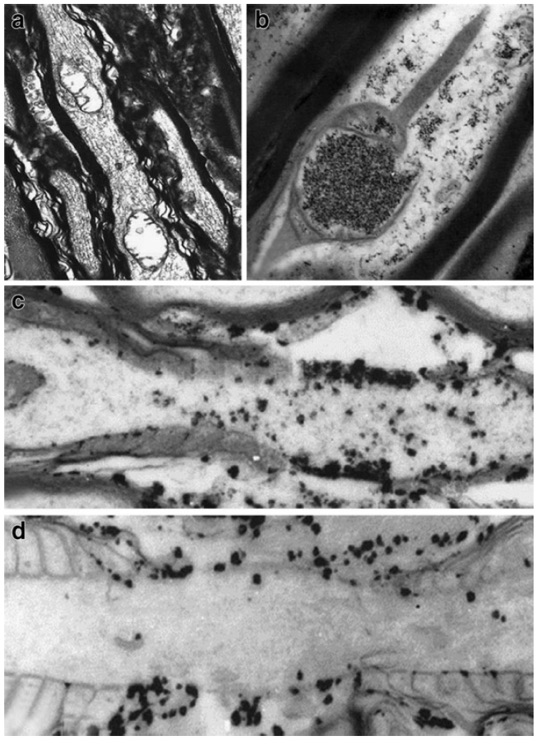

Figure 2 demonstrates evidence of calcium petrification of mitochondria in the upper right image with subsequent vacuolization in the upper left image in an animal model of mTBI. In addition, the lower two images represent pre- and post-disruption of the sodium/potassium pump following axonal stretching in the same model. Chronically, this ongoing disease process may progress to involve neurodegenerative changes associated with amyloid and tau protein, as well as parenchymal loss (atrophy). (6,7)